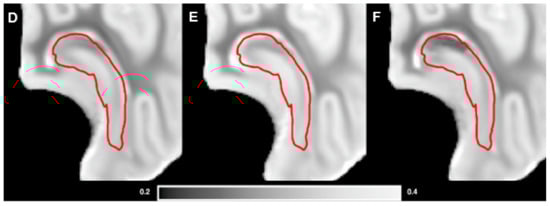

3.3. Brain Weights, Water Content and MRI Analysis